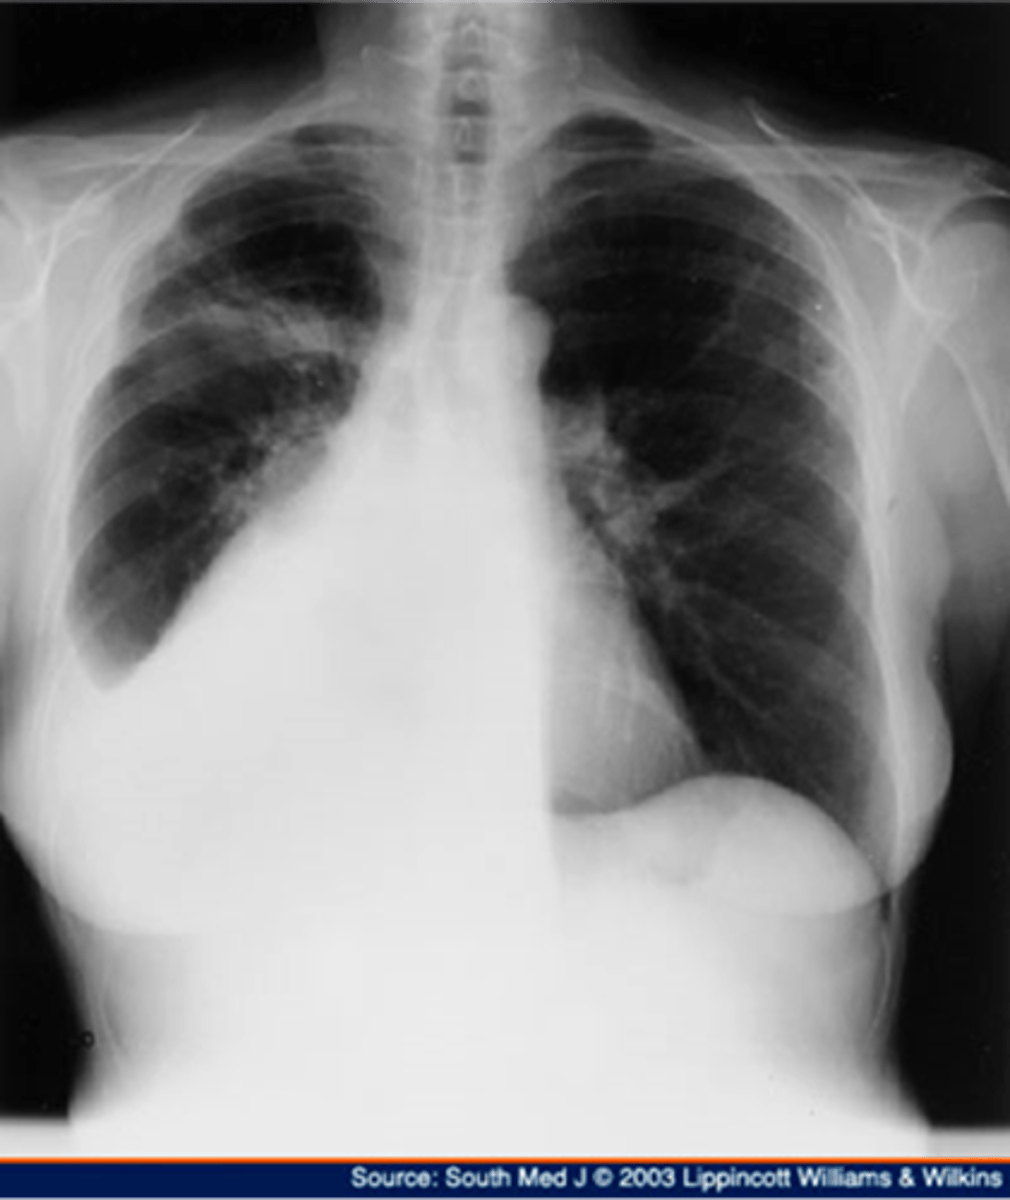

Pleural effusion

knowt flashcard image

Pleural effusion (right sided)